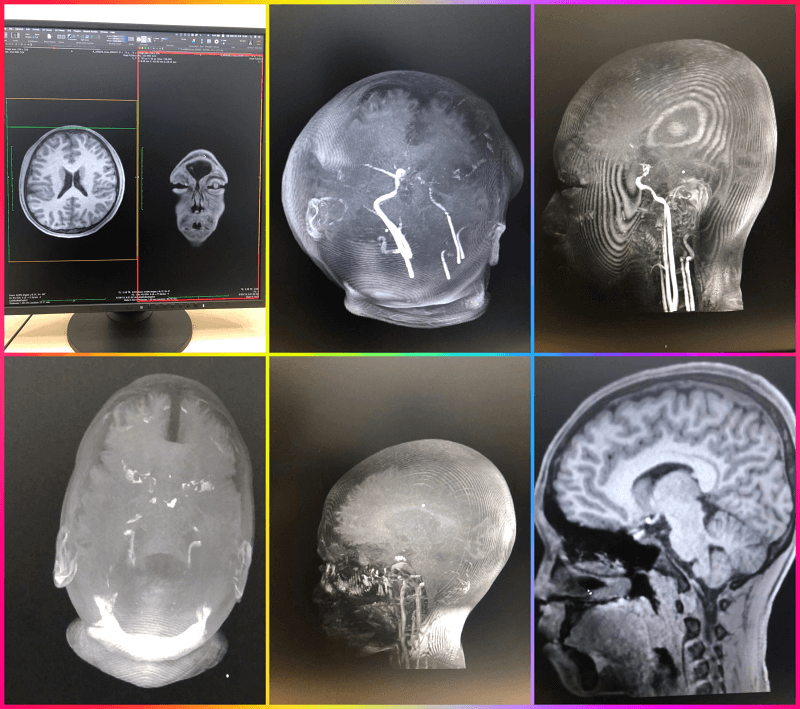

뇌과학 연구를 위해 한 대학교에 가서 찍은 아들의 뇌의 모습입니다. 실제로 두상이 예쁠 줄 알았는데 보는 것과는 많이 다르고 예쁜 두상을 가진 자녀들의 모습을 보는 순간 어렸을 적 관리를 잘해 줄 걸 하면서 후회가 막 밀려왔습니다.

사람의 뇌를 실제로 영상 품질이 높은 화면으로 보면 정말 신기하고 가느다랗고 투명한 실로 모두가 연결이 된 것을 보면서 신비로움은 이루 말할 수 없는데요 솔직하게 손발 눈 등도 신비롭지만 명령을 내리는 역할을 하므로 보이는 사진보다 더 투명하고 아름답게 보였습니다.

뉴로 게이 져 이흥렬 대표 : 뇌는 30살까지 최고 성장을 하고 그 이후부터는 성장을 멈추고 퇴화에 들어갑니다. 헉~~~ 깜짝 놀랐어요 제 나이가 그때 40대였으니 슬프기도 했습니다. 뇌를 위에서 상하로 움직이면 오른쪽에서는 위에서 바라보는 모습이 바뀌는 것을 보면서 신기하기도 했다

뇌의 위에서 찍은 모습이 마치 산호 밭이 모두가 연결된 것처럼 아주 투명하게 보인다

위 사진은 한 대학교 연구를 위해 참여 신청을 하고 촬영을 위해 어떤 약물을 먹고 3시간여 동안 촬영을 하면서 어떤 강점이 사람별로 있는지를 모듈화 하기 위해서 촬영한 부분인데 일정의 DNA가 어떤 강점을 가지고 있는지 다른 각도에서 사람마다 투명한 하얀색의 라인들이 모두 다르고 크기가 다른 것들을 비교해서 같이 참여했던 친구들과 볼 수가 있었는데 나중에 어른이 되어서 추적관리도 가능하다고 했고 자녀들까지도 어떤 구조로 성장을 하고 있는지를 추후에 파악을 한다고 이야기를 들었다

유명하신 뇌연구 이대열 교수님 동생인 뉴로 게이저 이흥열 대표가 정상인의 뇌의 정보를 구축하는 연구에 아들 참여 신청해서 검사를 했었는데 벌써 몇 년 전인데 지금까지 그 데이터를 모으고 벵크화 하는데 시간을 보낸 것 같아 연구의 길은 너무 힘들어 보입니다.